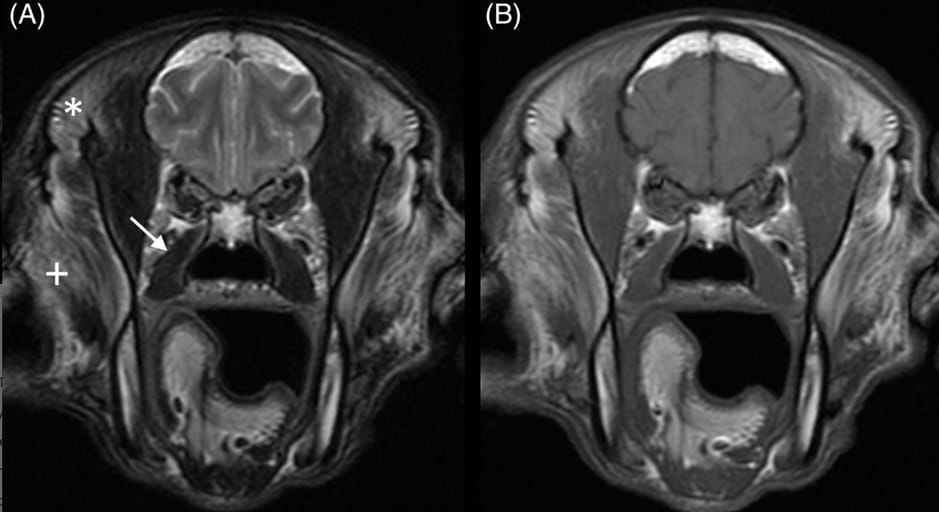

Transverse T2W (A) and T1W (B) high-field image of the head of a 10-year-old basset hound with severe, bilaterally symmetrical hyperintensity in the superficial part of the temporalis muscles (*) and the dorsal aspect of the masseter muscles (+) as well as mild atrophy of the temporalis muscles. The parts of the temporalis muscles deep to the mandibular coronoid processes are spared. The pterygoid muscles appear normal (arrow)